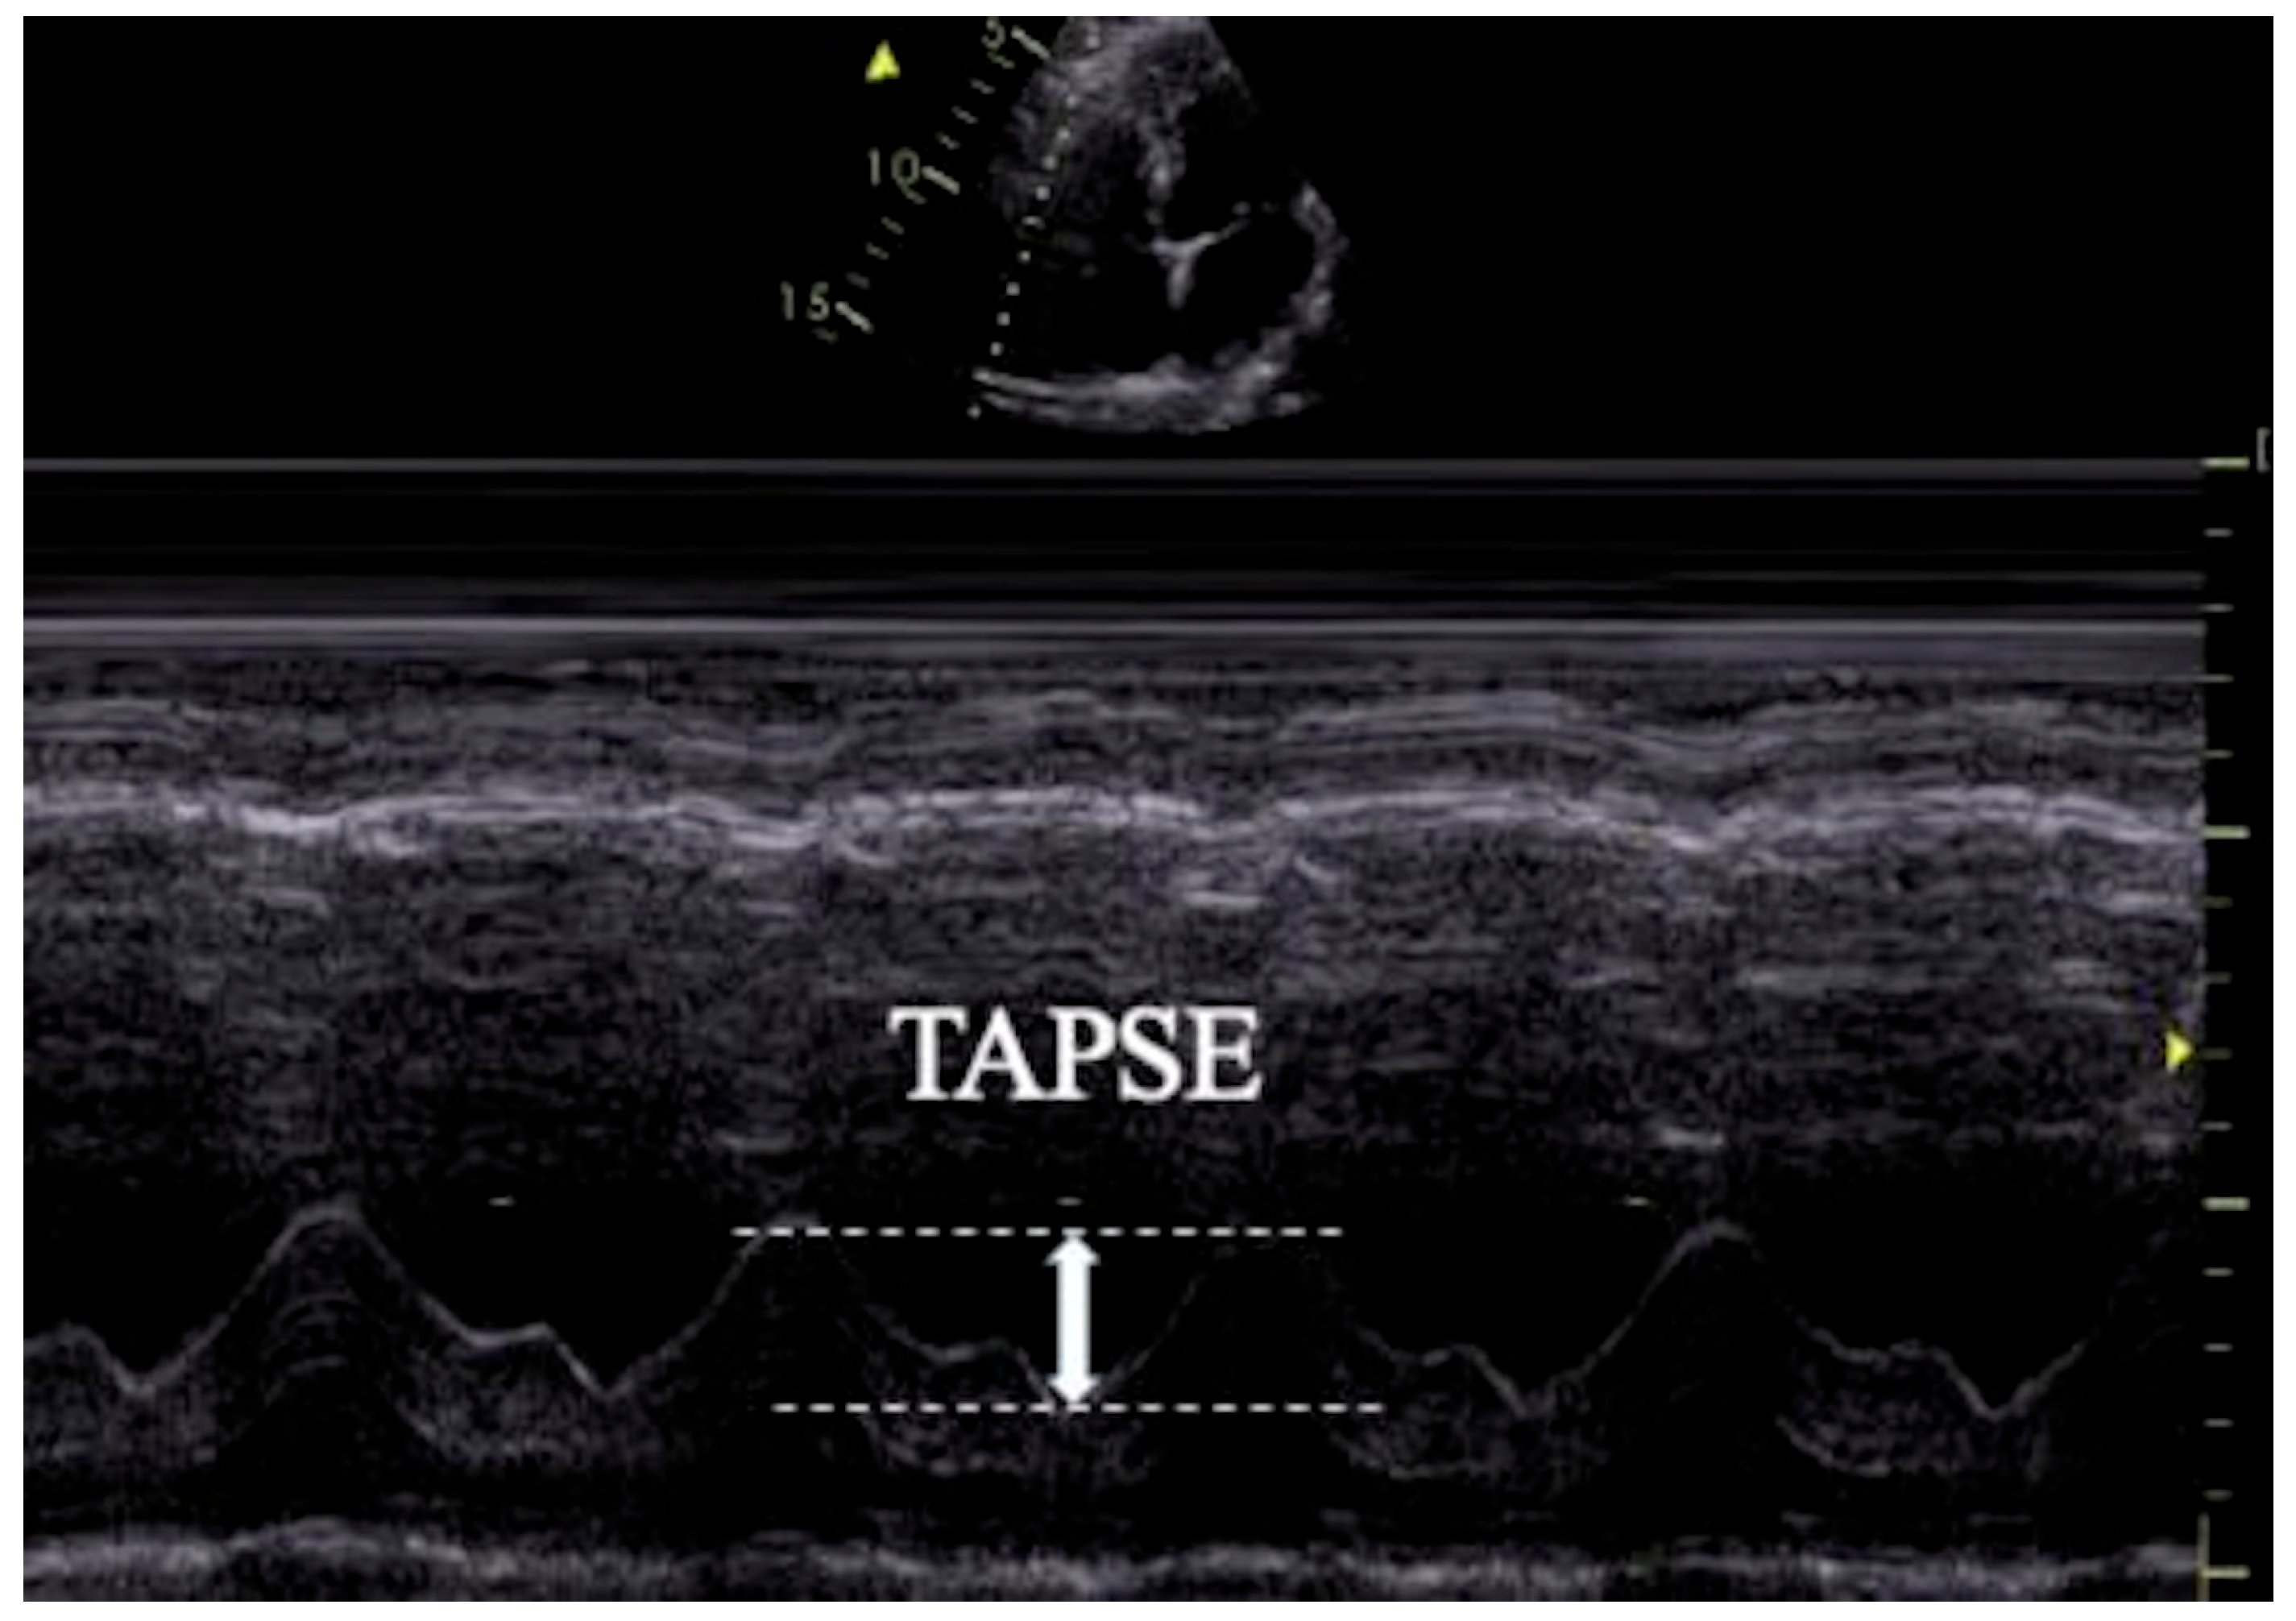

2.3. Transthoracic Echocardiography (TTE) and Data Collection

| TAPSE | 25.75 ± 3.23 | 22.17 ± 2.68 | <0.001 |

| TAPSE/PASP | 2.29 ± 0.81 | 1.63 ± 0.68 | <0.001 |

| TAPSE/PASP | ≤1.988 | 0.725 | 0.641 | 0.366 | 0.733 (0.621–0.826) | <0.001 |

| TAPSE | ≤23.13 | 0.725 | 0.795 | 0.520 | 0.807 (0.703–0.887) | <0.001 |